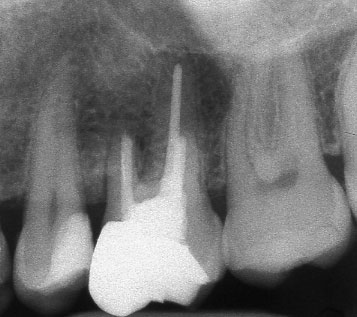

Рентгенографии на добре пролекувани зъби

Ако при диагностична рентгенография се установи, че даден канал не е запълнен до физиологичното стеснение, е необходимо да се проведе повторно ендодонтско лечение.

В някои случаи недобре запълненият коренов канал е показание дори за отстраняване на протезни конструкции (корони и мостове) в които е включен съответният зъб.